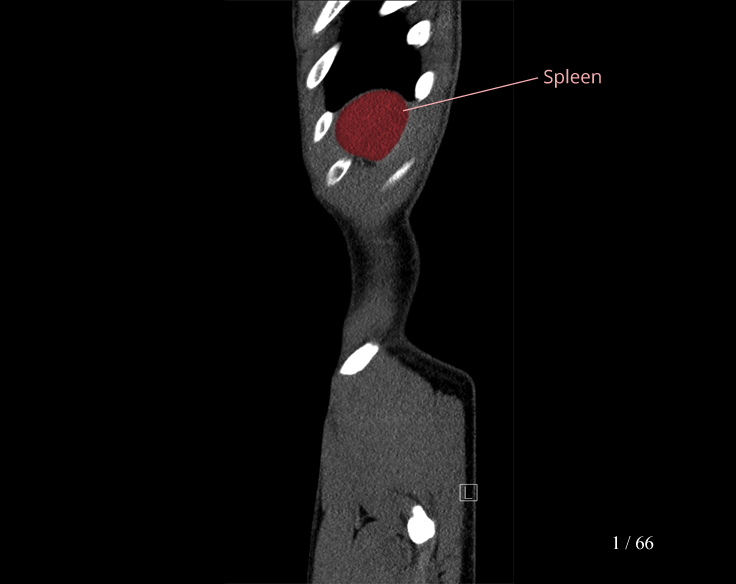

Body

Covers abdominal CT anatomy.